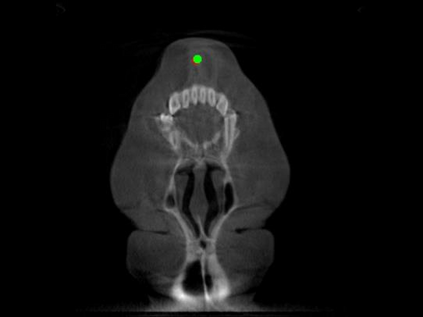

Detecting 3D landmarks on cone-beam computed tomography (CBCT) is crucial to assessing and quantifying the anatomical abnormalities in 3D cephalometric analysis. However, the current methods are time-consuming and suffer from large biases in landmark localization, leading to unreliable diagnosis results. In this work, we propose a novel Structure-Aware Long Short-Term Memory framework (SA-LSTM) for efficient and accurate 3D landmark detection. To reduce the computational burden, SA-LSTM is designed in two stages. It first locates the coarse landmarks via heatmap regression on a down-sampled CBCT volume and then progressively refines landmarks by attentive offset regression using multi-resolution cropped patches. To boost accuracy, SA-LSTM captures global-local dependence among the cropping patches via self-attention. Specifically, a novel graph attention module implicitly encodes the landmark's global structure to rationalize the predicted position. Moreover, a novel attention-gated module recursively filters irrelevant local features and maintains high-confident local predictions for aggregating the final result. Experiments conducted on an in-house dataset and a public dataset show that our method outperforms state-of-the-art methods, achieving 1.64 mm and 2.37 mm average errors, respectively. Furthermore, our method is very efficient, taking only 0.5 seconds for inferring the whole CBCT volume of resolution 768$\times$768$\times$576.